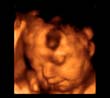

3-D Technology Helps Expecting Mothers Discover Their Unborn Children